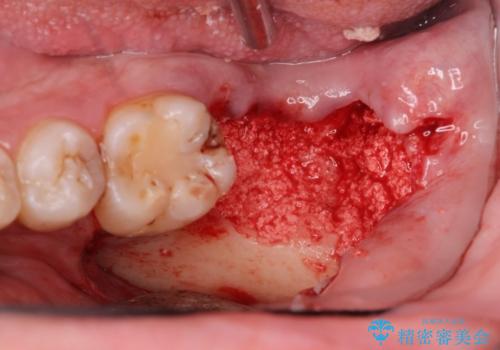

まず徹底的に虫歯を取り除き、保存が出来ない部位は抜歯(親知らずを含む)を行い、根管治療が必要な部位は精密根管治療を行いました。

その後、インプラント治療、セラミック治療を行いました。

また、虫歯が歯肉の中まである場合はAPF(歯肉弁根尖側移動術)も行なっています。